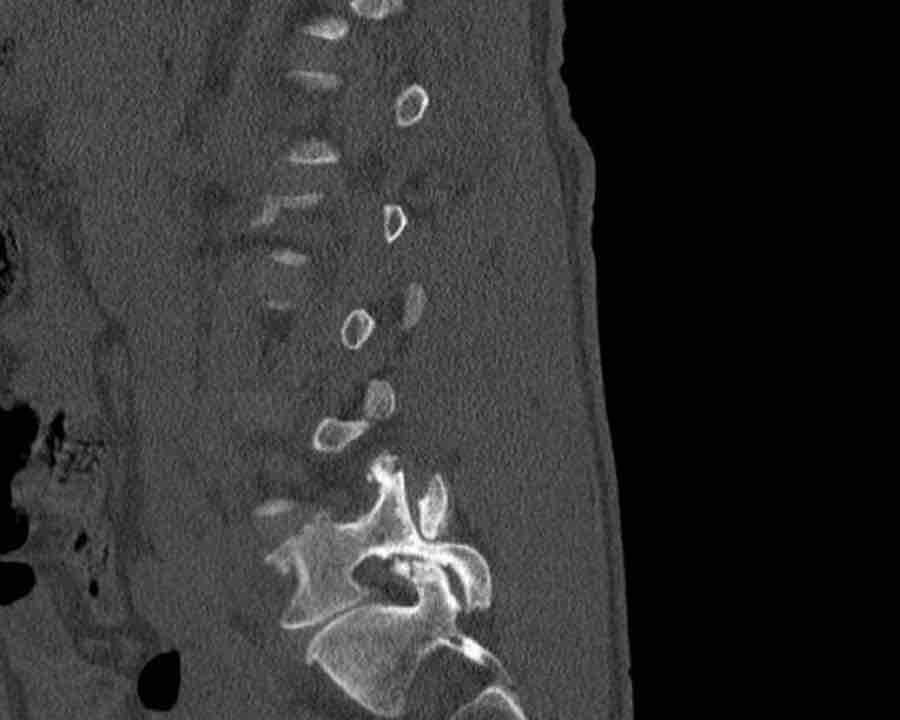

Scroll through the images

Findings:

- Perched facet joints (yellow curved arrows), so think of C injury.

- Posterior displacement of the vertebral bodies in the midline.

- Secondary A4 injury of the vertebral body.

Conclusion

Type C + A4 injury